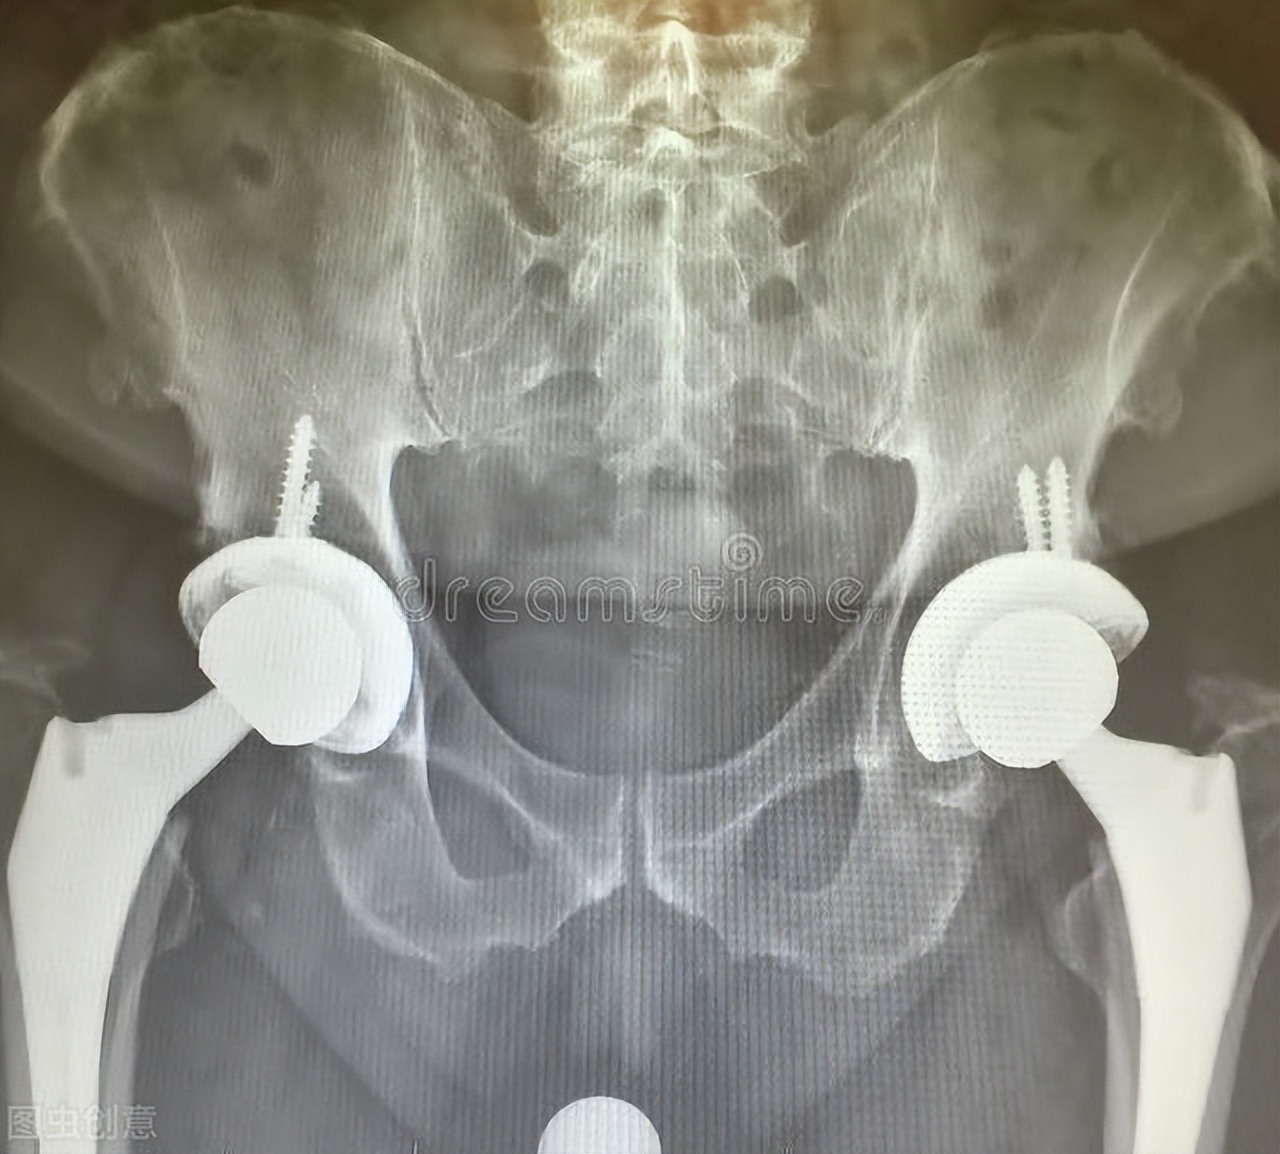

今天收了一个94岁做完股骨头置换手术的病人,家属告诉我因为老大爷在家不小心摔了一跤,来医院拍片子一看,骨折了,还好老人平时身体还算健朗,没什么特别的基础疾病,排除手术禁忌及麻醉禁忌等后,做完了手术,现在到我们科室康复一下。那么问题来了,老年人骨头脆,很多人年龄大了,就开始骨质疏松了,怎么办?